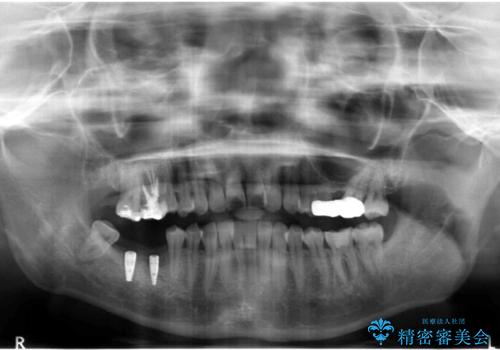

- 奥歯が虫歯で他院で抜かないといけないといわれ来院。

虫歯を放置していたが、これを機にしっかり通って治したいとのことでした。

右下は虫歯がひどく、抜歯が必要でした。また、右下の一番奥の歯は親知らずのため使うことができない状態でした。